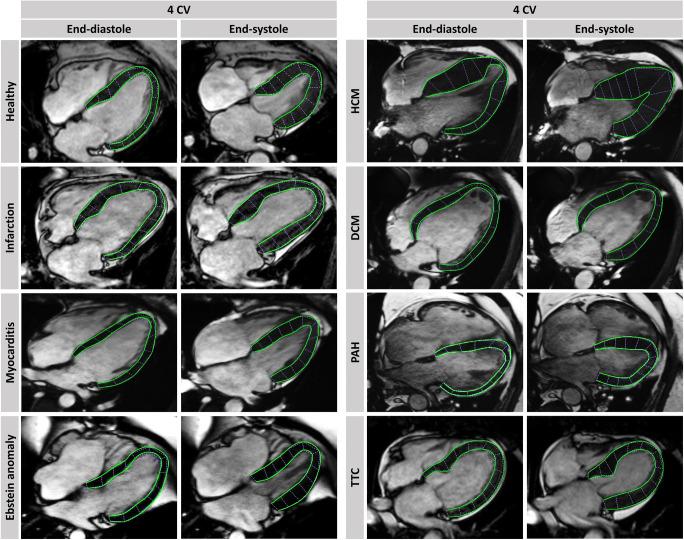

Cardiac magnetic resonance-feature-tracking (CMR-FT)-based deformation analyses are key tools of cardiovascular imaging and applications in heart failure (HF) diagnostics are expanding. In this review, we outline the current range of application with diagnostic and prognostic implications and provide perspectives on future trends of this technique.

By applying CMR-FT in different cardiovascular diseases, increasing evidence proves CMR-FT-derived parameters as powerful diagnostic and prognostic imaging biomarkers within the HF continuum partly outperforming traditional clinical values like left ventricular ejection fraction. Importantly, HF diagnostics and deformation analyses by CMR-FT are feasible far beyond sole left ventricular performance evaluation underlining the holistic nature and accuracy of this imaging approach. As an established and continuously evolving technique with strong prognostic implications, CMR-FT deformation analyses enable comprehensive cardiac performance quantification of all cardiac chambers.